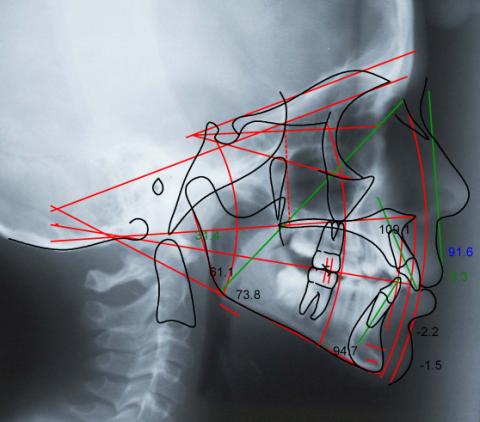

SML Digital stands ready to receive your patient’s digital files via our secure, HIPAA-compliant, password-protected SML Digital Portal. Once we receive your patient’s digital data, our diagnostic staff will assist you with your patient consultations, diagnoses, treatment planning and case presentations. Whether you are beginning to integrate appliance therapy into your practice or are an experienced veteran at orthodontics, we will provide you with the information you need to successfully complete each treatment.

SML Diagnostic Services include: